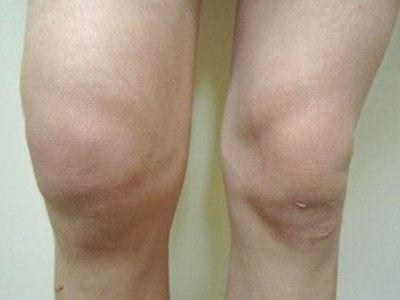

膝关节创伤性滑膜炎是指膝关节外伤后发生的膝关节滑膜无菌性炎症反应,急性损伤性膝关节滑膜炎,可发生于任何年龄。本病以关节疼痛、肿胀为主要临床表现。

膝关节创伤性滑膜炎可表现为局部胀痛,在膝关节完全伸直或属曲时胀痛感更明显,此外,由于局部淤血,可导致局部出现青紫色。局部可逐渐出现关节肿胀,并伴有活动受限、压痛等症状。